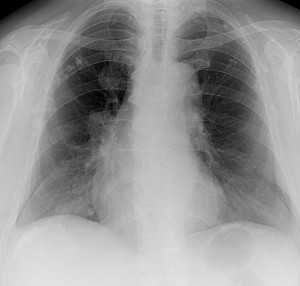

Метастазы в легких — фото рентгенограммы. Округлые тени — метастазы рака пищевода. Хорошо виден большой узел округлой формы вблизи переднего отрезка 2-го ребра. На снимке справа - циркулярное сужение пищевода за счет опухолевого утолщения его слизистой оболочки.

Как выглядят метастазы в легких на рентгене? Слева — узловые образования у пациента с раком яичка. Справа - метастазы рака яичников гематогенного характера с выраженным опухолевым лимфангиитом (обратите внимание на деформированный сетчатый, линейный характер легочного рисунка).